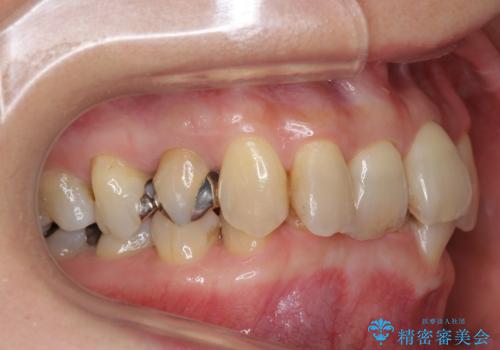

かみ合わせが深く、上の歯が咬みこんで下の歯にワイヤーがつけられない状態で、ワイヤー矯正はかなり難しい状態でした。

かみ合わせが深い方はもともとかみしめが強く、マウスピース矯正を長期にすると、奥歯が咬まなくなってくる症状が強くなります。

今回もそういった状態になったのを、装着時間や歯の移動を工夫する形で治療しました。